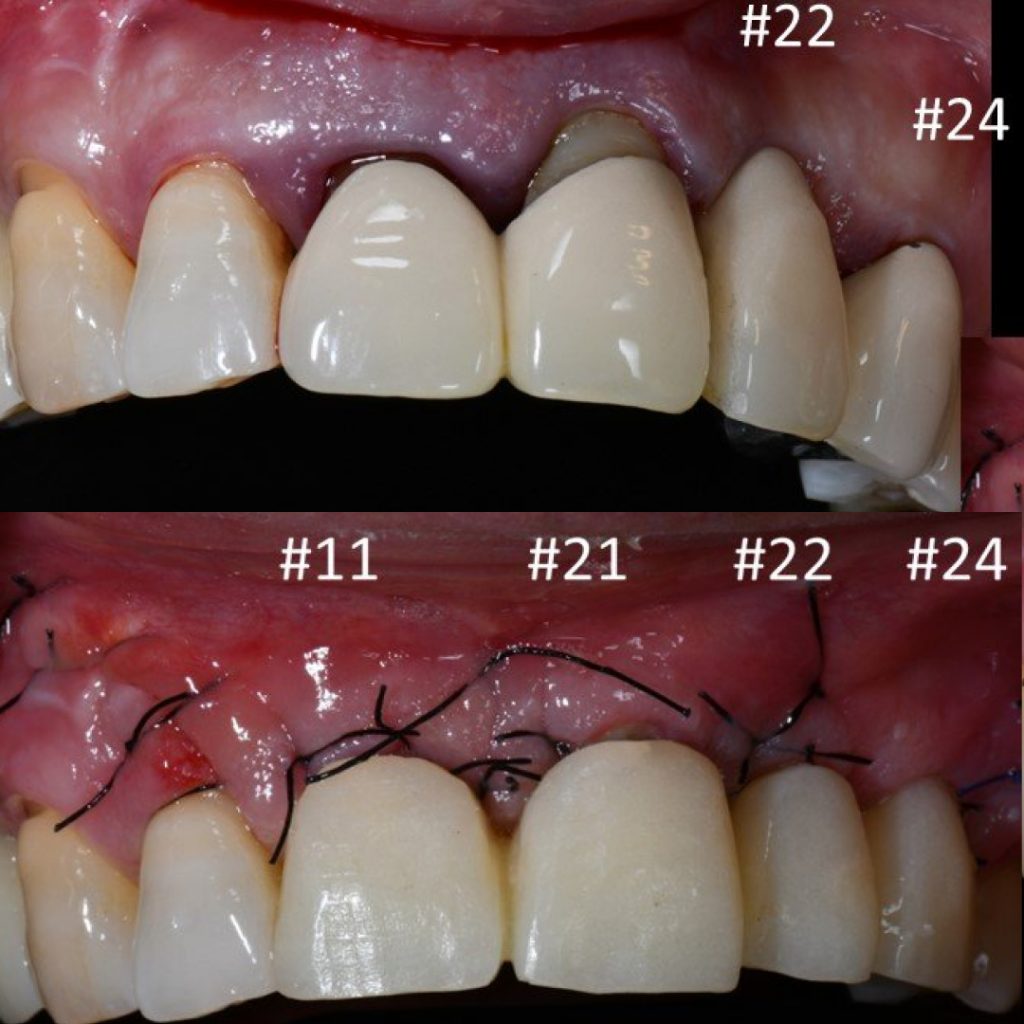

- Установка абатментов для временного протеза

- Покрытие зоны аугментации коллагеновой мембраной

- Фиксация временного мостовидного протеза

Благодаря уникальному дизайну имплантатов AnyRidge становится возможным получить блестящую первичную стабильность даже при наличии объемных костных дефектов, что позволяет в большинстве случае дать немедленную нагрузку на имплантаты и зафиксировать временный мостовидный протез

в эстетически значимой зоне в день операции.